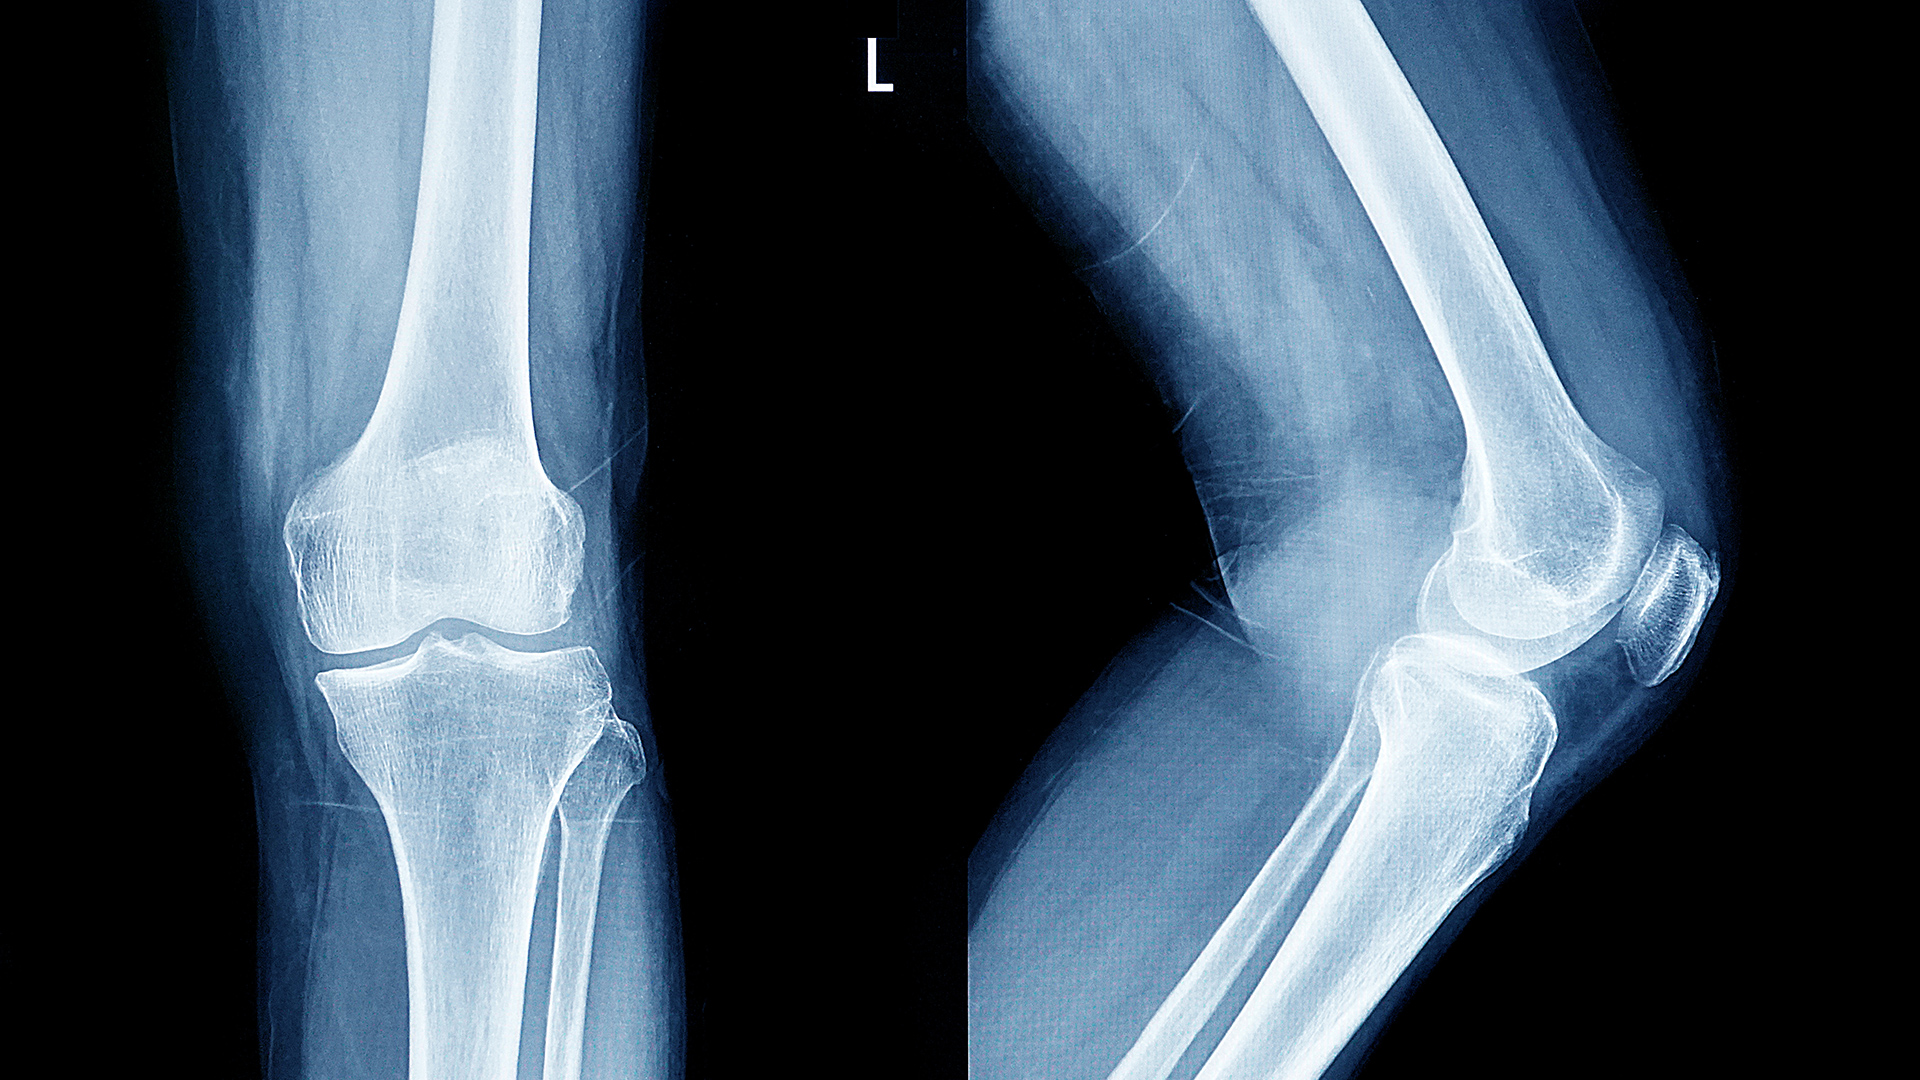

ما هي هشاشة العظام؟

وتؤدي هشاشة العظام إلى ضعف العظام وزيادة قابليتها للكسر، وغالبًا ما تُكتشف بعد حدوث كسر مفاجئ نتيجة سقوط بسيط أو إصابة خفيفة.

وتشمل الكسور الأكثر شيوعًا:

كسر الرسغ

كسر الورك

كسور فقرات العمود الفقري